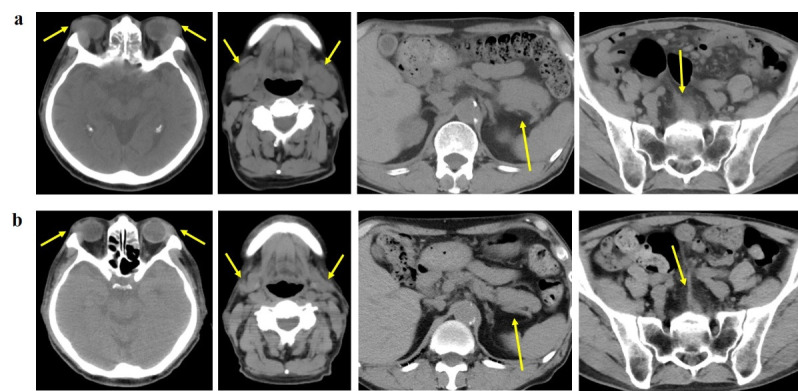

18F-FDG PET/CT is regarded as a modality utilized for the purpose of lesion localization, staging and assessment of treatment response in patients with lymphoma. However, it is difficult that we diagnose among multifocal lymphoma, IgG4-related disease (IgG4-RD), or a combination of both conditions when confronted with multiple sites of 18F-FDG uptake with heightened serum IgG4 levels. We present a case of a 72-year-old male who was suspected of Sjögren's syndrome based on symptoms of xerostomia accompanied by swelling of the bilateral upper eyelid and salivary glands. Following a diagnostic biopsy that revealed mucosa-associated lymphoid tissue (MALT) lymphoma as a possible finding, 18F-FDG PET/CT was conducted, which demonstrated multiple sites of 18F-FDG accumulation. While multifocal MALT lymphoma was initially suspected, the coexistence of IgG4-RD could not be definitively ruled out due to the elevated serum IgG4 levels. Subsequent histopathological and immunohistochemical examinations confirmed the diagnosis of IgG4-producing MALT lymphoma. After receiving systemic therapy with rituximab, the swelling of the bilateral upper eyelid and parotid glands resolved upon visual examination, and the serum IgG4 levels returned to within the normal range in a few months. No new lesions were detected during the subsequent follow-up examinations conducted over a period of 3 years.